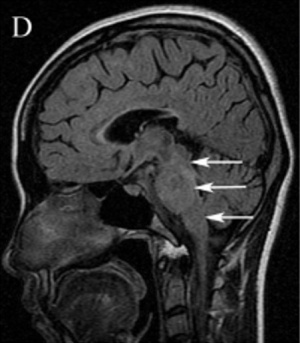

Neuroimaging is helpful in diagnosing ADEM. At presentation, MRI findings may be similar between MS and ADEM. In patients with ADEM, T2-weighted and fluid attenuated inversion recovery (FLAIR) brain MRI typically shows large, bilateral, hyperintense, lesions (>1-2 cm) that are diffuse and poorly demarcated.[22] ADEM lesions can involve both the white and gray matter, affecting the subcortical and central white matter, cortical gray-white matter junction, and deep gray matter of the basal ganglia, thalami, cerebellum, brainstem, with very rare T1 hypointense “black hole” white matter lesions that are more typically seen in MS.[14][22] Gadolinium enhancement of ADEM lesions is found in only 30% of cases.[35]

Key brain MRI features found in ADEM that are absent in MS include periventricular sparing without Dawson fingers (ovoid lesions perpendicular to lateral ventricles), both deep gray matter and cortical involvement, bilateral and diffuse lesions that are large, globular, and poorly demarcated.[22] In 1/3 of cases, spinal cord demyelination is seen over multiple segments. Diffusion-weighted imaging (DWI) can help elucidate the timing of the demyelinating event.[39] In the first week following ADEM onset, DWI will show decreased diffusivity. This is thought to be a result of inflammation causing myelin sheath edema and accumulation of inflammatory cells, impeding the migration of water molecules. After the first week, the extracellular space widens, causing increased water diffusivity on DWI.[39]